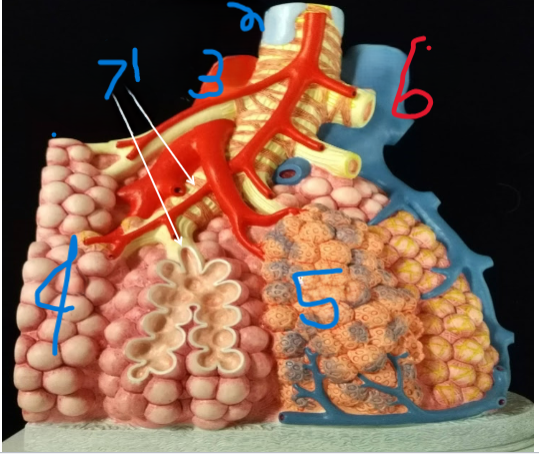

Terminal Bronchiole

What is depicted by #1

Bronchiole with smooth muscle

What is depicted by #2

Pulmonary vein, branch

What is depicted by #3

Alveoli

What is depicted by #4

Pulmonary capillaries

What is depicted by #5

Pulmonary artery, branch

What is depicted by #6

Respiratory Bronchiole

What is depicted by #7